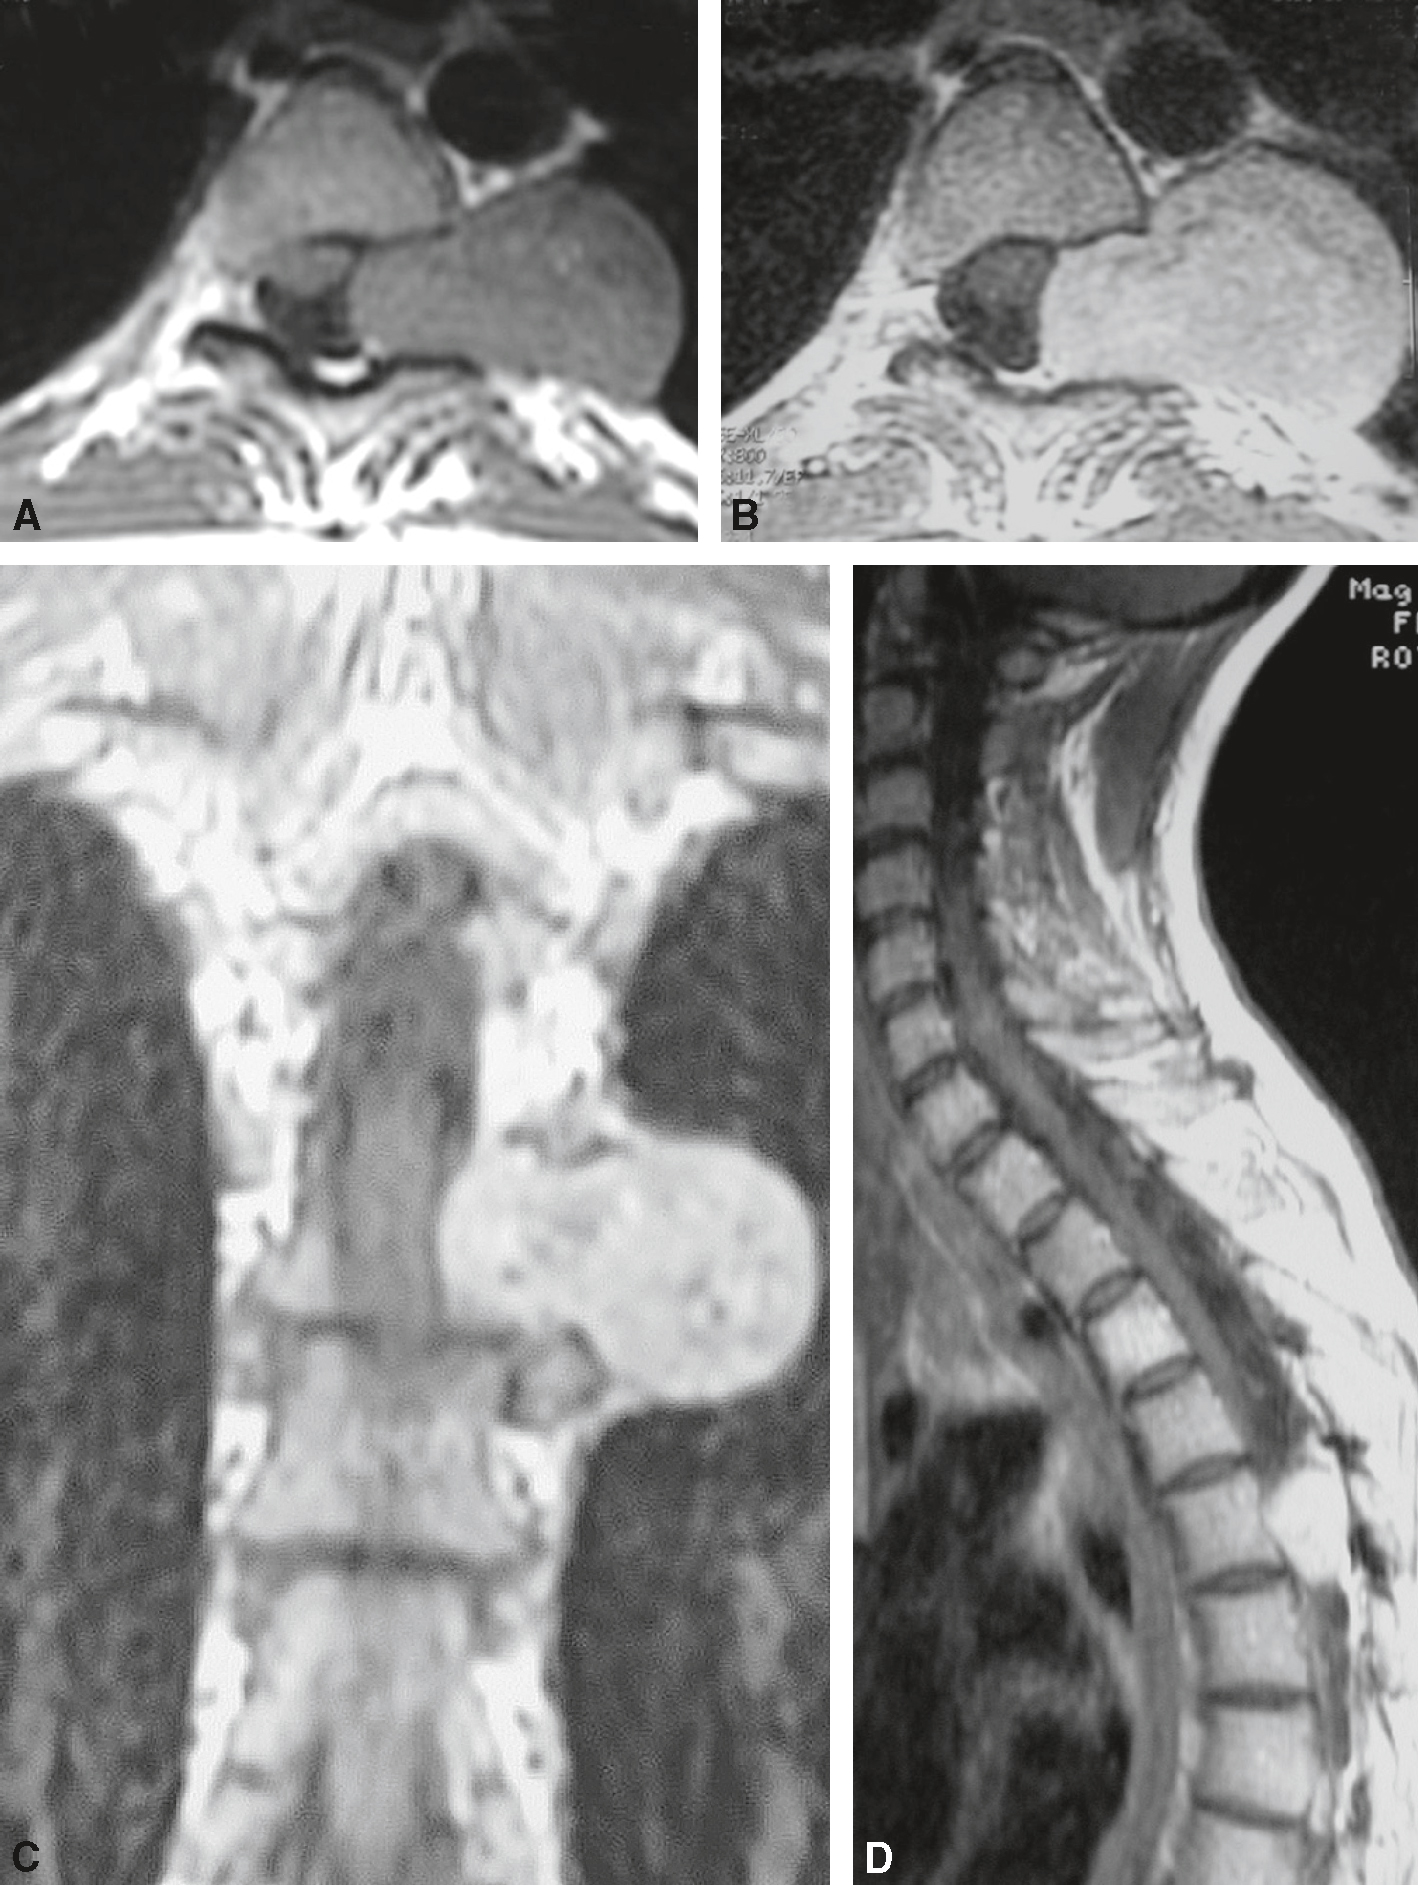

• Les causes extradurales sont dominées par les métastases néoplasiques vertébrales pouvant être compliquées d’une épidurite métastatique (fig. 7.3) :

Fig. 7.3

Métastase vertébrale avec épidurite.

Lésion osseuse développée au niveau du corps de T4, massivement étendue aux pédicules et à l’arc postérieur à gauche (coupe axiale), en hyposignal T1, en hypersignal T2, fortement rehaussée après injection de gadolinium. Extension intracanalaire épidurale avec compression et engainement médullaires. Les espaces liquidiens péri-médullaires sont totalement effacés en regard de la compression. À noter, le respect des disques intervertébraux sus- et sous-jacents. A. T1 sagittal après injection. B. T2 sagittal. C. T1 sagittal. D. T1 axial après injection.Série d’images en imagerie par résonance magnétique (IRM) en coupes sagittales et axiales illustrant une métastase vertébrale compliquée d’une épidurite. Les coupes sagittales (A, B et C) montrent une infiltration pathologique d’un corps vertébral thoracique avec un hyposignal en T1 et un hypersignal en T2, traduisant un envahissement tumoral. Un effet de masse est visible, avec effacement du signal normal de la graisse épidurale postérieure et compression de la moelle épinière. L’image D en coupe axiale confirme la compression épidurale avec déformation circulaire de la moelle et envahissement des tissus périmédullaires. L’aspect évoque une épidurite secondaire à une localisation métastatique, nécessitant une prise en charge urgente pour prévenir un déficit neurologique.